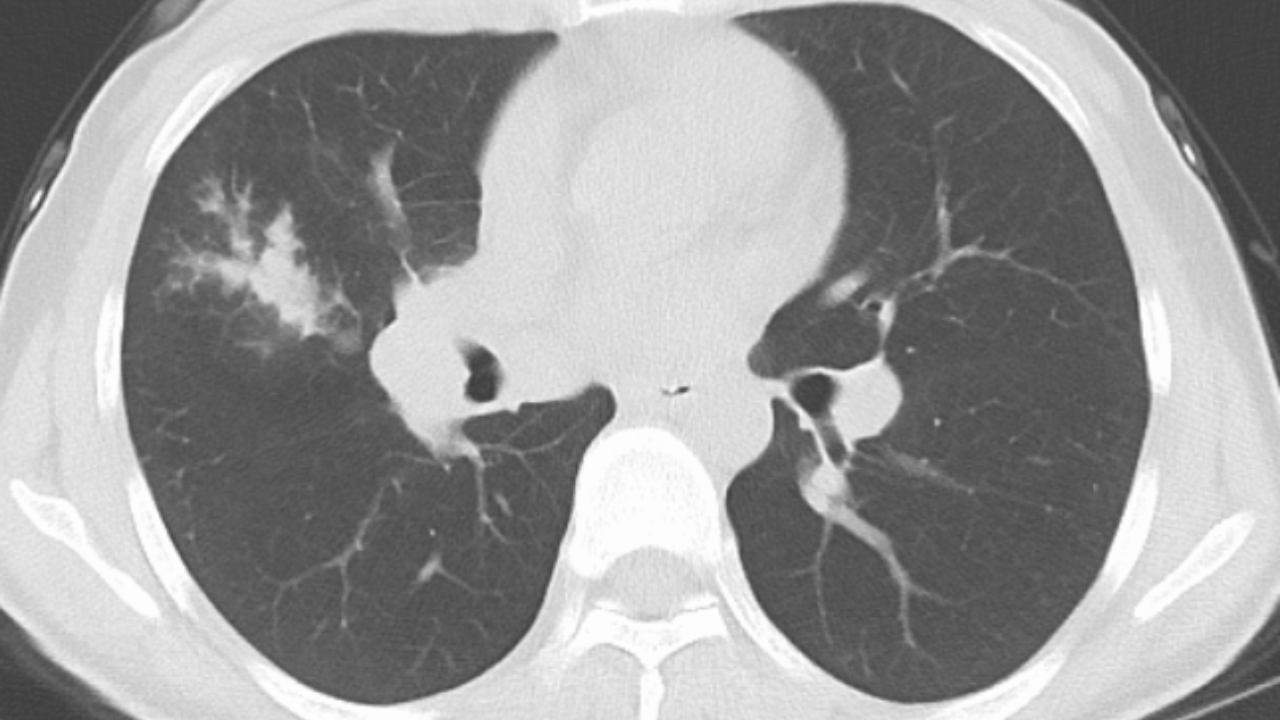

女性35岁,主因咳嗽、咳痰1月,胸部CT报肺炎,猜对乃神医!

女, 35 岁,主因咳嗽、咳痰1月于2025-11-05 08:46入院。

1.现病史:患者中年 女,患者于入院前1月“感冒”后出现咳嗽、咳痰,为黄白痰,不易咳出,无痰中带血,咽部刺痒不适,咳嗽明显,无胸痛,无胸闷、憋气,无恶心,未呕吐,无腹痛、腹泻,无尿频、尿急、尿痛,于院外口服药物(具体不详)治疗,病情未见好转,2025-11-4于我院门诊查胸部CT提示右肺炎症。为进一步诊治来我院;门诊以“肺炎”收入院 。

3.查体:T36.5℃,P90次/分,R18次/分,BP105/65mmHg。神清,呼吸平稳,浅表淋巴结不大,双肺叩清音,双肺呼吸音粗,右肺可闻及湿性啰音,左肺未闻及干湿性啰音,心率90次/分,心律齐,无杂音。腹部平坦软,全腹无压痛,无反跳痛及肌紧张,肝脾肋下未触及,双下肢无水肿。

肺炎。